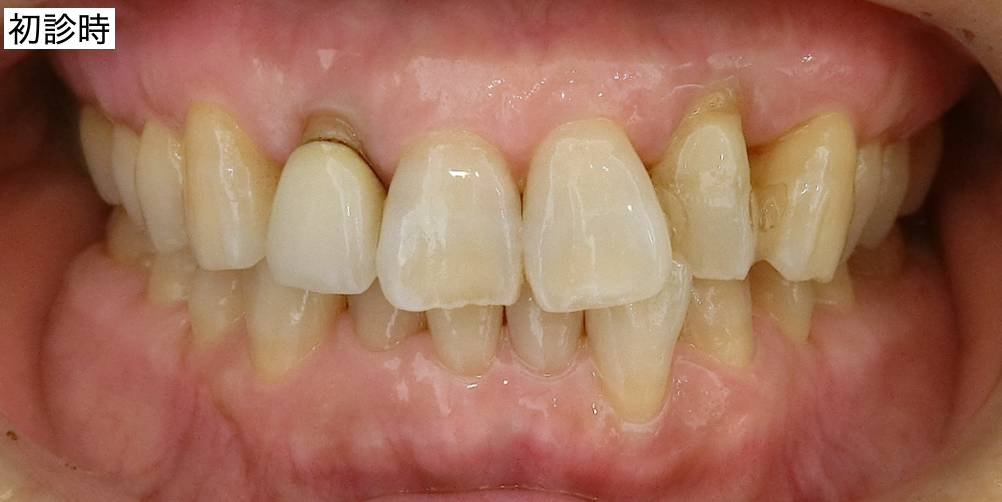

前回、全体的に治したいと来院された患者さんに問題点とその治療計画、手術計画を提案し、同意頂きました。

上部構造装着後です。

各々の部分の比較です。まず右上です。